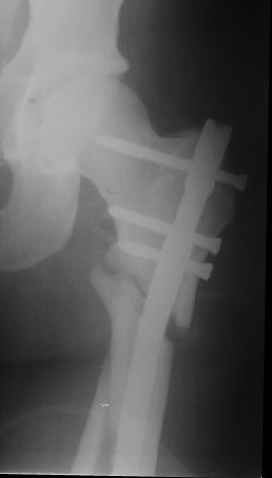

При межвертельных переломах с цефаломедуллярными гвоздями бывает, что проксимальый винт проходит или черед периферический отломок, или прямо над ним. И если остался диастаз, то этот винт при осевой нагрузке не дает сблизиться отломкам. Пример такого остеосинтеза в застарелом случае в приложении.

В качестве предупреждающей меры можно долотом разрушить латеральную стенку дистального отломка под винтом.